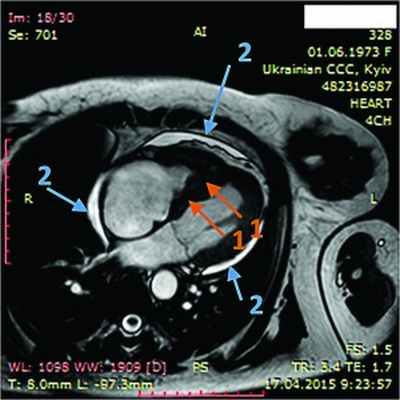

Рис. 1. Синусовая тахикардия. Желудочковые экстрасистолы (ЭС). Отклонение электрической оси сердца вправо. Отсутствие амплитудной динамики низковольтного зубца R в грудных отведениях

Рис. 2. Неравномерное значительное утолщение стенок ПЖ (парастернальный доступ, позиция по длинной оси)

Рис. 3. Тромб у верхушки ПЖ, уплотнение между листками перикарда в области верхушки (четырехкамерная позиция сердца)

Рис. 4. Сохраненная кинетика стенок ЛЖ, гидроперикард по ЗСЛЖ (парастернальный доступ, позиция по длинной оси, М-режим)

Рис. 5. Рестриктивный транстрикуспидальный кровоток (допплер)

Рис. 7. Динамическая томография, боковая проекция с контрастированием эндокарда (1) и тромба ПЖ (2)

Рис. 8. Динамическая томография, поперечная проекция с контрастированием полостей и тромба в ПЖ (1), гидроперикарда по всем стенкам (2)

Рис. 9. Динамическая томография, поперечная проекция с контрастированными полостями и стенками – неравномерное утолщение миокарда желудочков (1) с двумя апикальными тромбами (2)

Рис. 10. Динамическая томография, боковая проекция с контрастированием полостей и стенок – апикальный тромб ЛЖ

Рис. 11. Динамическая томография, косая проекция с контрастированием полостей и стенок – апикальные тромбы ЛЖ

В ходе серии динамических МРТ с контрастированием (рис. 7-11) выявлены массивные пристеночные тромботические наслоения в ПЖ, апикальный тромб ЛЖ.